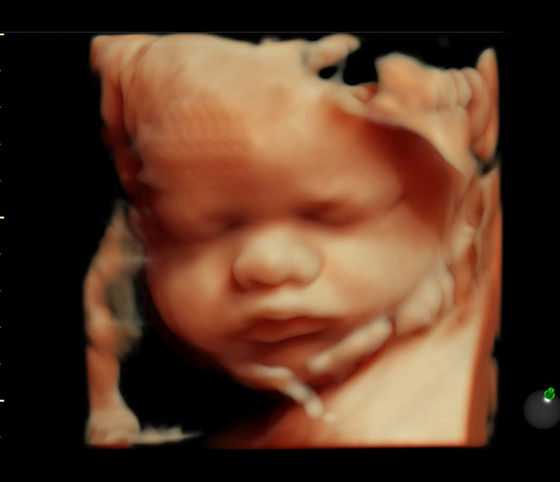

3、人流完备的术前检查非常重要,通过这些术前检查,一方面可以确定受术者是否有妇科炎症或其他生殖道疾病,以避免手术过程中造成感染;另一方面可以确定孕囊的大小、位置、妇性生殖道及宫腔是否有异常情况等,可以大降低手术过程中的风险,一旦发生意外情况可以及时有效的处理;另外,术前检查可以明确受术者是否有心脏病史?是否适合麻醉?是否贫血等等一系列问题,对于降低手术风险也是非常必要的。一般来说,人流手术前检查主要包括妇科检查、B超检查、白带常规、心电图、血常规及血液分析等。